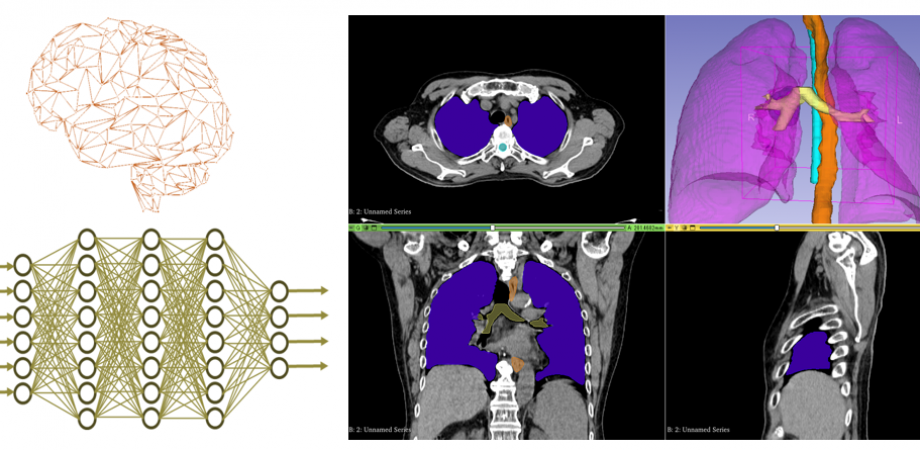

医用画像におけるAIの活用は今後ますます増加すると予想されます。そこで今研修会では、AIの活用方法として既に現場で利用されている放射線治療計画における自動輪郭抽出について、現在の臨床現場での活用例、そのあとは実際にPythonの画像処理フレームワークであるMONAIを使った実習を通して、臨床現場のアプリケーションの活用だけでは理解できないAIの動きを体験してもらうことで自動輪郭抽出の理解を深めるような研修会となっております。

実習内容 胸部CT画像を用いた自動輪郭抽出